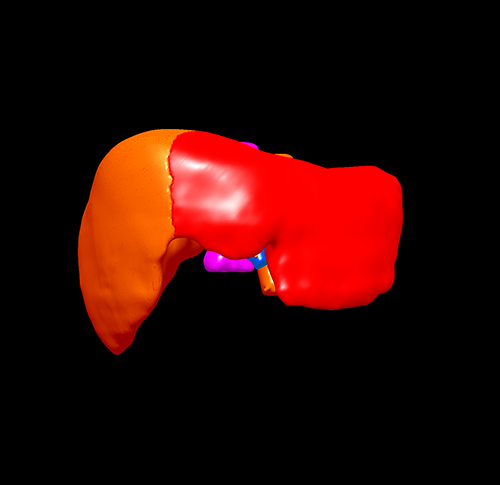

S678肝癌 ---腹腔镜右半肝切除